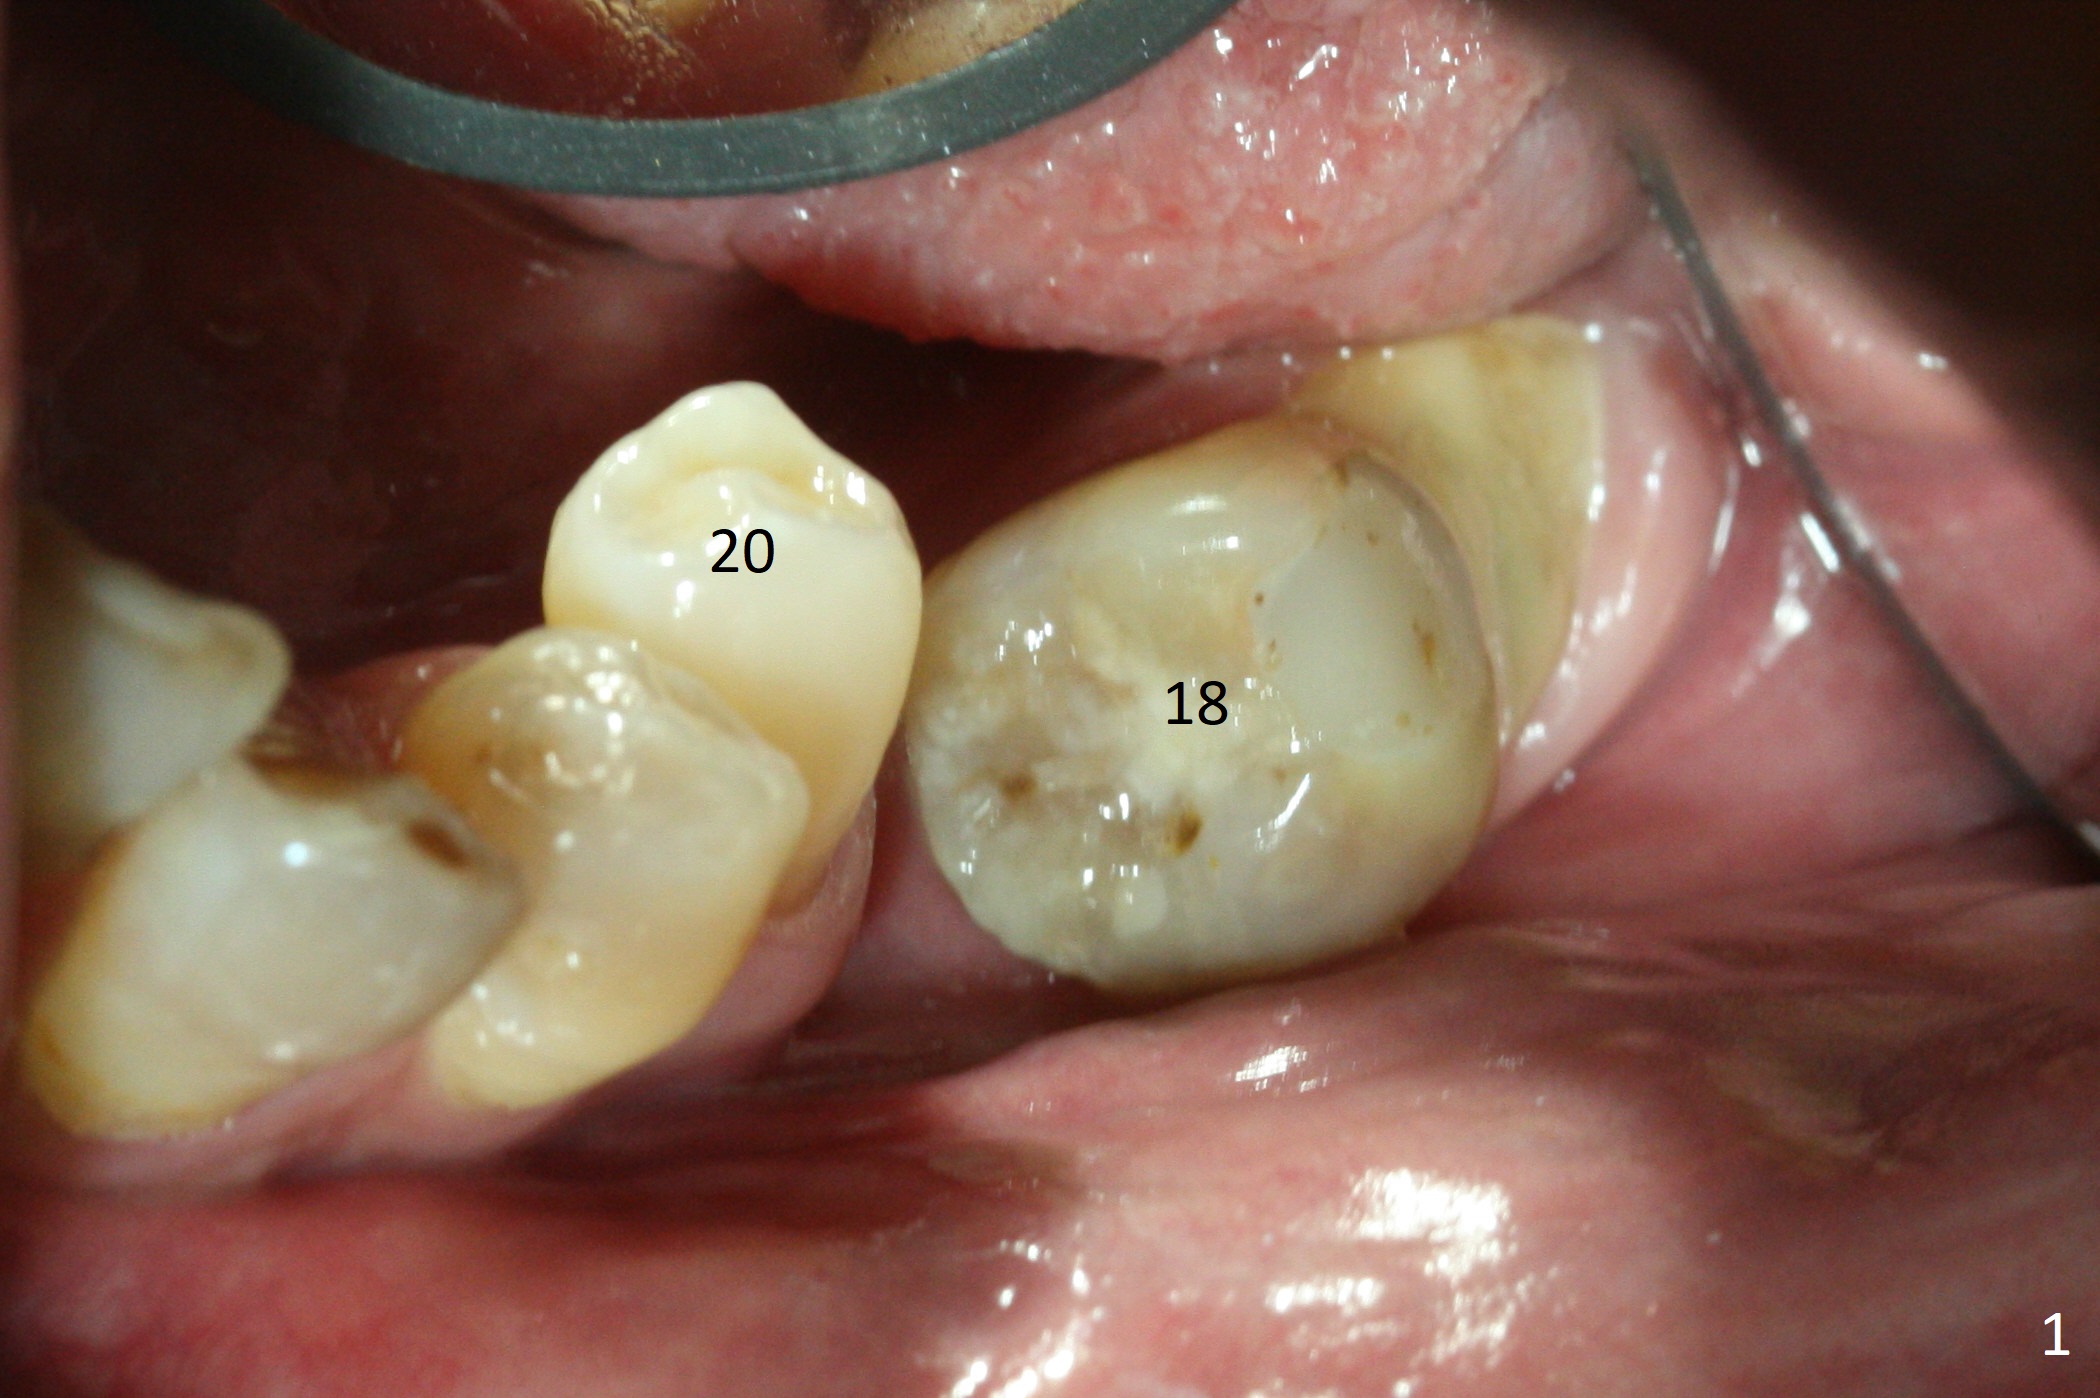

Preop photo shows severe mesial tilt of the tooth #18 (Fig.1). After extraction, the osteotomy is established in the apical end of the socket, where the buccolingual width is limited. It appears that an extra wide implant (5.9 mm) may perforate one of buccolingual plates. On the other hand, the buccal plate (Fig.2 double arrows) is intact and approximately 2 mm tall, whereas the lingual one is thin and lower. Initial osteotomy confirms that bone heights at #18 and 19 are 6 and 8 mm, respectively. Counting 2 mm of the buccal plate and bone graft lingually, a 8 mm long implant may be a practical option at the site of #18. After initial placement of two of 5x8 mm SM implants (Fig.3), the depth of the implant at #19 is adjusted twice (Fig.4,5). With placement of autogenous and allograft (Vanilla, Fig.5 *)) and abutments, a piece of cotton pellet is placed in each abutment well (access, Fig.6 *). Periodontal dressing is applied to the abutment wells for additional retention (Fig.7 *). Due to local poor oral hygiene, splinted provisional is fabricated 4 months postop (Fig.8) in preparation for limited orthodontic uprighting the tooth #20. The patient has pain with mastication at #18 eleven months post cementation (Fig.9). It appears that both of the implants should be removed with immediate replacement and bone graft. Prepare 4 PRF and sticky bone. The new implant will be 5.0 or 5.5x5 mm (Fig.10 green) with 2.3 mm platform (white). A block graft will be harvested from the ipsilateral ramus using 9/8 and 6/5 mm trephine burs for 2-3 mm in depth (Fig.11 blue). The ring graft will be seated around the platform over the implant (Fig.12).